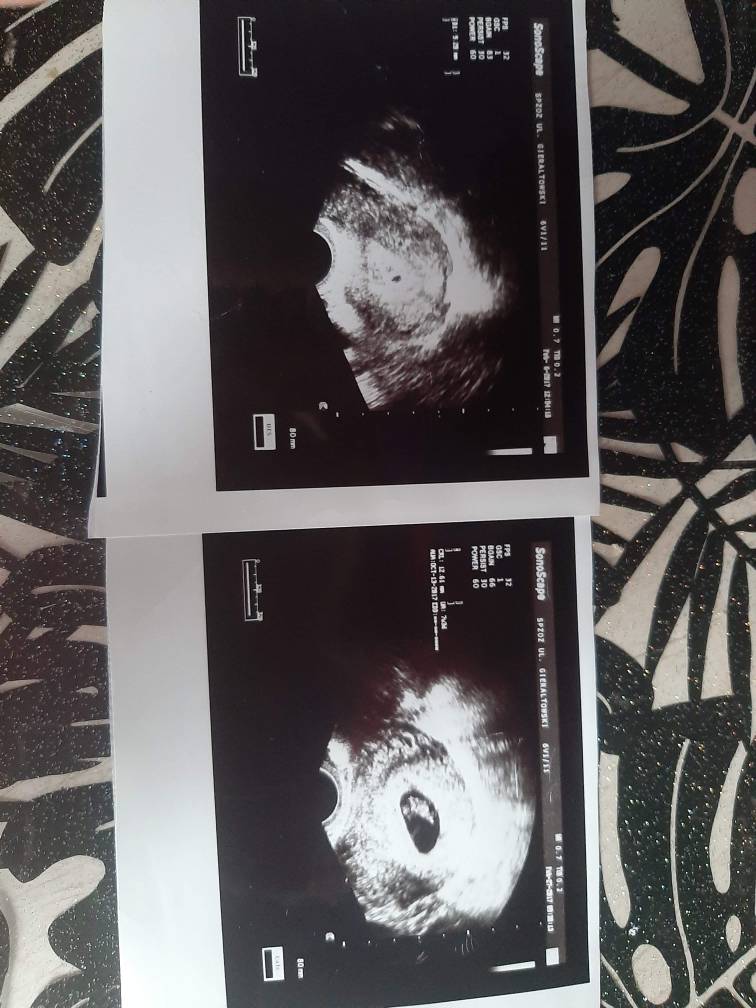

Hej dziewczyny :-) kiedyś pisałam Wam o mojej ciąży , że wynik był dodatni (beta 701) ale później niestety okazało się że to była ciąża biochemiczna. To był cykl wrześniowy. Teraz jestem w kolejnym cyklu . Czekam na okres który ma być za dwa dni. Po tamtej ciąży biochemicznej , byłam u lekarza , wszystko ładnie się oczyściło tylko na lewym jajniku pojawiła się torbiel krwotoczna . Więc dziś byłam na badaniu usg na kontroli tej torbielki. Okazało się że zmalała i nie trzeba się nią przejmować . ALE CO MNIE ZASKOCZYLO dziewczyny! Pani wykonująca usg powiedziała że moje endometrium wskazuje że mogę być w ciąży i że jest ciałko żółte😲 a ja do niej że to niemożliwe bo owulację wg usg po ciąży biochemicznej miałam mieć z lewego jajnika który jest niedrożny ! A ona że owulacja była z prawego :confused: Myślę sobie : "jak to drugi raz z prawego ?" . No ale dobra . Kazała zrobić betę to ja siup na badanko . Wynik po 15:00. Odbieram a tu <1,20 . :oo2: zaskoczyłam się i wkurzyłam bo niepotrzebnie mi narobiła nadziei :confused2: